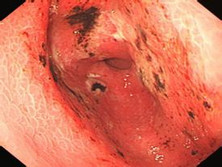

急性糜烂出血性胃炎

急性糜烂性胃炎是一种以胃粘膜多发性糜烂为特征的急性胃炎,又称急性胃粘膜病变或急性...